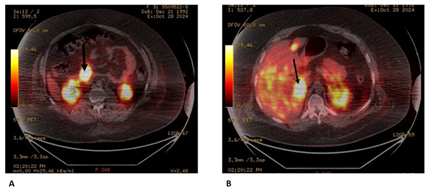

A 33-year-old man with a history of psychiatric pathology treated with risperidone since childhood. In the previous three years, he presented multiple episodes of symptomatic hypoglycaemia that required hospital admission and management with continuous infusion of glucose serum, with blood glucose values that reached 35 mg/dl, seizures and loss of consciousness, which require management in intensive care. During the evaluation, a computed tomography of the abdomen was requested, which showed 2 pancreatic lesions, one in the body of 28 mm and another in the uncinate process of 42 mm. Additionally, multiple focal lesions were found in the liver, the largest of which was 32 mm (Figure 1). Likewise, venous glycemia of 37 mg/dl, insulin of 137 (normal range 2 to 12 μU/mL) and increased C-peptide of 8.27 (normal range 1.1 to 4.4 ng/ml) were found, which allowed a diagnosis of malignant insulinoma with liver metastases. A PET-CT scan with 18F-NOTATOC confirmed that pancreatic and hepatic lesions expressed somatostatin receptors (Figure 2a and 2b).

Figure

2:

PET with 18F-NOTA-OCT

A: insulinoma

uptake is observed (arrow);

B: uptake of

multiple liver metastases and the largest one (image on the right)